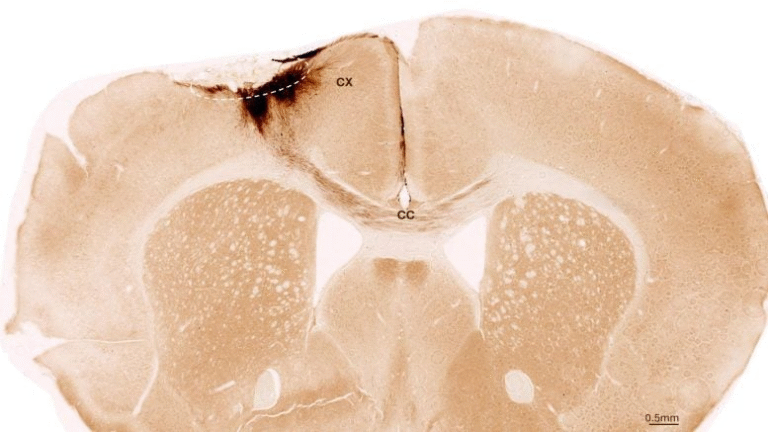

The study specifically focused on cholecystokinin-expressing interneurons (CCK-INs) in the dentate gyrus region of the hippocampus. These neurons are glucose-inhibited, meaning their activity levels are strongly influenced by how much glucose is available in the brain.

When the brain’s glucose dropped due to the high-fat diet, these CCK-INs became hyperactive. This excessive activity disrupted normal hippocampal rhythms and impaired memory processing in the mice.